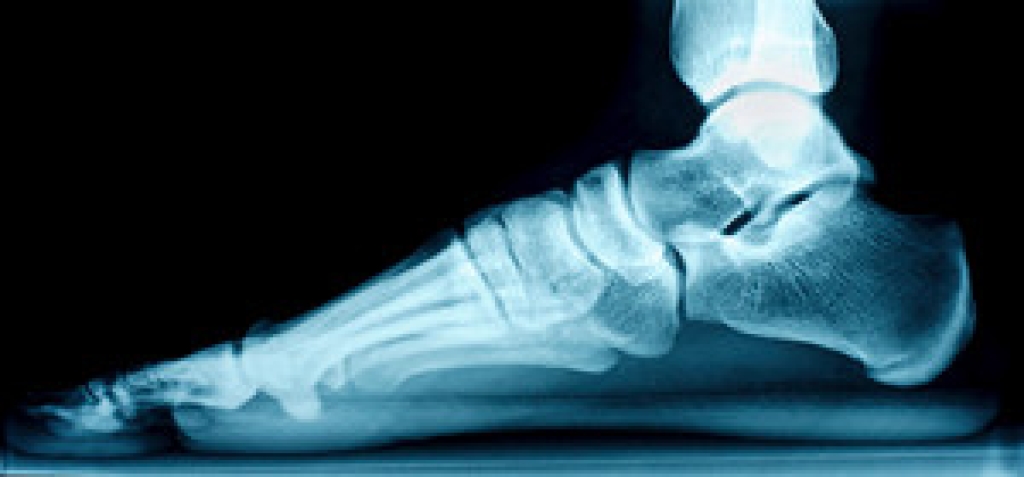

One of the most common foot deformities is called a hammertoe. This means the middle joint of the toe pops up instead of lying flat. Hammertoe usually affects the 2nd, 3rd, and 4th toes and can become painful as the protruding joint rubs against the inside of the shoe. Causes of hammertoe vary, but the most common is wearing high-heeled shoes with pointy-toes. Not surprisingly, more women develop hammertoe than men. Trauma from a fall or blow, sprains, or broken toes can all contribute to the formation of a hammertoe as well. They also can be caused by side effects from arthritis, diabetes, and polio. Hammertoe can make it difficult to walk, thereby affecting the gait and causing problems in other parts of the body. If you have developed a hammertoe, please consult with a podiatrist for an examination and possible remedies available to you.

Hammertoe is a foot deformity that occurs due to an imbalance in the muscles, tendons, or ligaments that normally hold the toe straight. It can be caused by the type of shoes you wear, your foot structure, trauma, and certain disease processes.